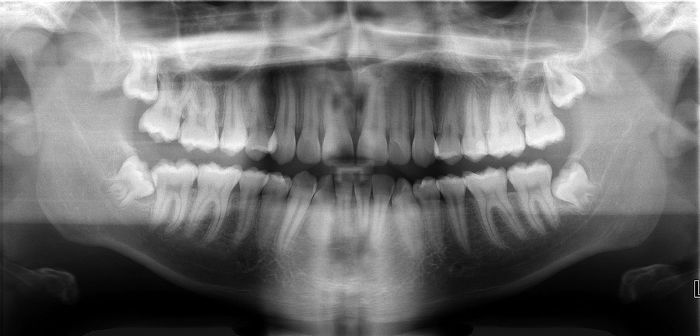

A. 치과에서 촬영하는 사진의 가장 대표적인 것은 '파노라마'라는 사진임. 서서 손잡이를 잡고 있으면 삐~ 같은 소리가 나면서 한 바퀴 돌아가서 나오는 사진이 바로 파노라마.

바로 이렇게 나오는 사진임

이 사진을 찍을 때 나오는 방사선 노출량= 1회에 0.011mSv

이 양이 어느 정도냐면 하루에 우리가 받는 방사선 량의 0.3%를 차지하는 비율임

그러니 치과에서 일주일이든 한달이든 한, 두번 촬영하는 파노라마 사진은 방사선 걱정 ㄴㄴ 해도 되는 부분